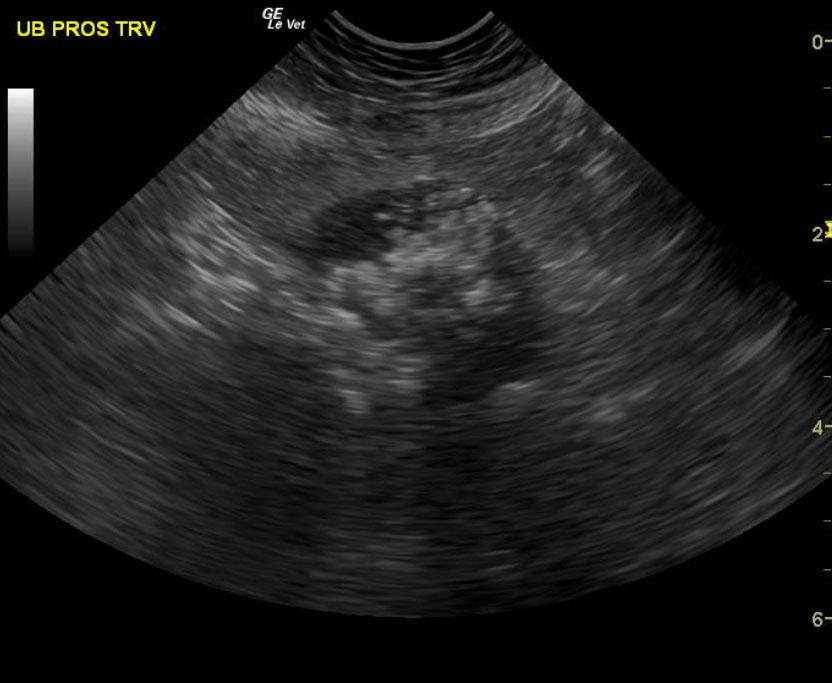

Mineralizing prostatic mass extending into the preprostatic urethra and trigone with local iliac lymphadenopathy. These images are strongly suggestive for metastatic prostatic carcinoma.

The prostate presented multi focal mineralization with swollen contour with minor polypoid changes and hyperechoic surrounding fat. This projected into the trigone. The mineralizing, prostatic mass measured 2.9 cm and infiltrated into the preprostatic urethra and likely post prostatic urethra. Iliac lymphadenopathy was noted.